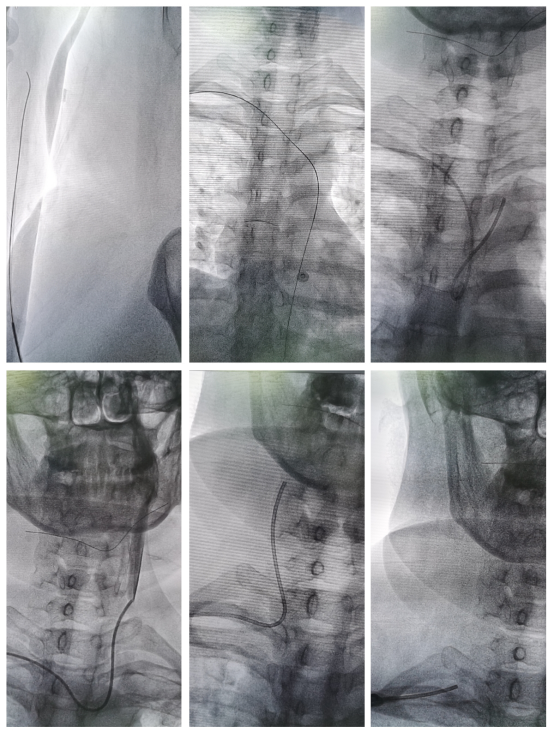

2022年4月16日,和田地区人民医院就收治了一位为明确病因的蛛网膜下腔出血的患者,患者为40岁女性,脑部CT血管成像未发现异常,为进一步明确患者脑血管是否存在动脉瘤等病因,北京天坛医院援疆医师罗岗和科里乃比江医师、迪力夏提等团队成员,对患者进行详细查体及进行Allen试验并确定结果阴性后,决定开展和田地区人民医院首例经桡动脉全脑血管造影术。

穿刺过程中罗岗向团队成员仔细介绍桡动脉穿刺细节及注意事项、穿刺成功后解痉药物的配比和用法用量,操作过程中仔细讲解手术导丝、导管器械的使用方法和技巧,历经25分钟手术顺利结束,术后罗岗告知团队伤口包扎方法和注意事项后,患者安放病房,入病房后,患者顺利下地行走,可独自完成饮食、大小便等日常生活,因脑血管造影未发现脑血管异常,告知患者及家属结果及复查注意事项后,患者次日清晨顺利出院。